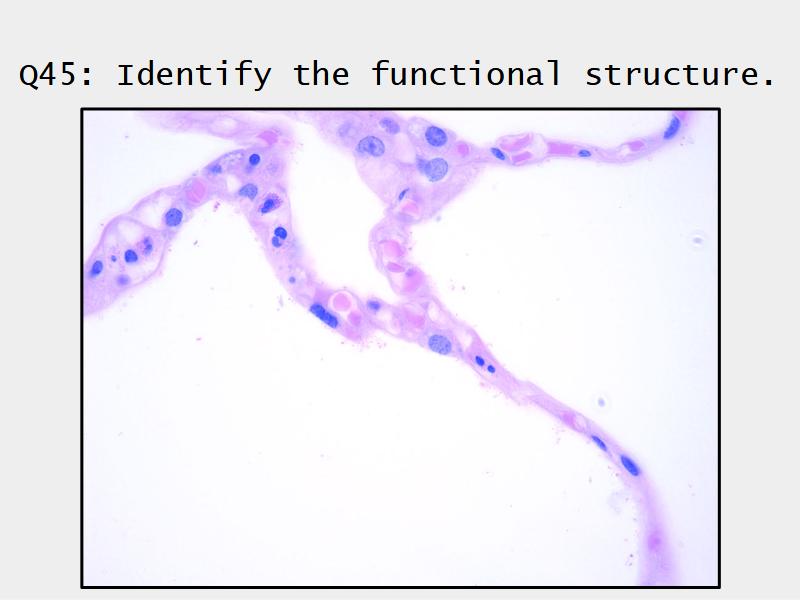

Components of the Blood-Air Barrier?

What other barrier systems are found in the body?

What are the purpose of each of these barrier systems? Connected with physiology will unlock the pathology.

Barriers

- Blood-air